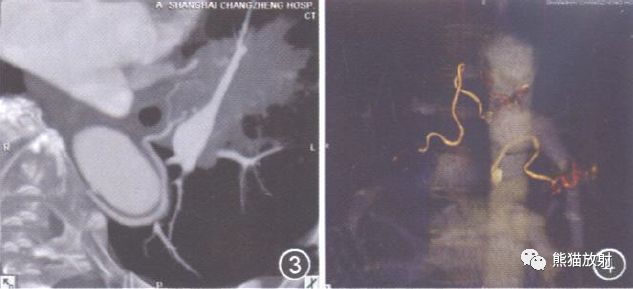

图5-8 右肺支气管扩张。图5为右主支气管MPR轴切面, 均分为4象限, 显示R1位于Ⅰ象限即支气管前缘, R2位于Ⅱ象限即支气管后缘;图6为CPR重组, 显示R2;图7(前后位)和图8(后前位)VR, 显示BA R2L1 型, R1源自右锁骨下动脉, R2源自降主动脉右侧壁, L1源自降主动脉右侧壁。